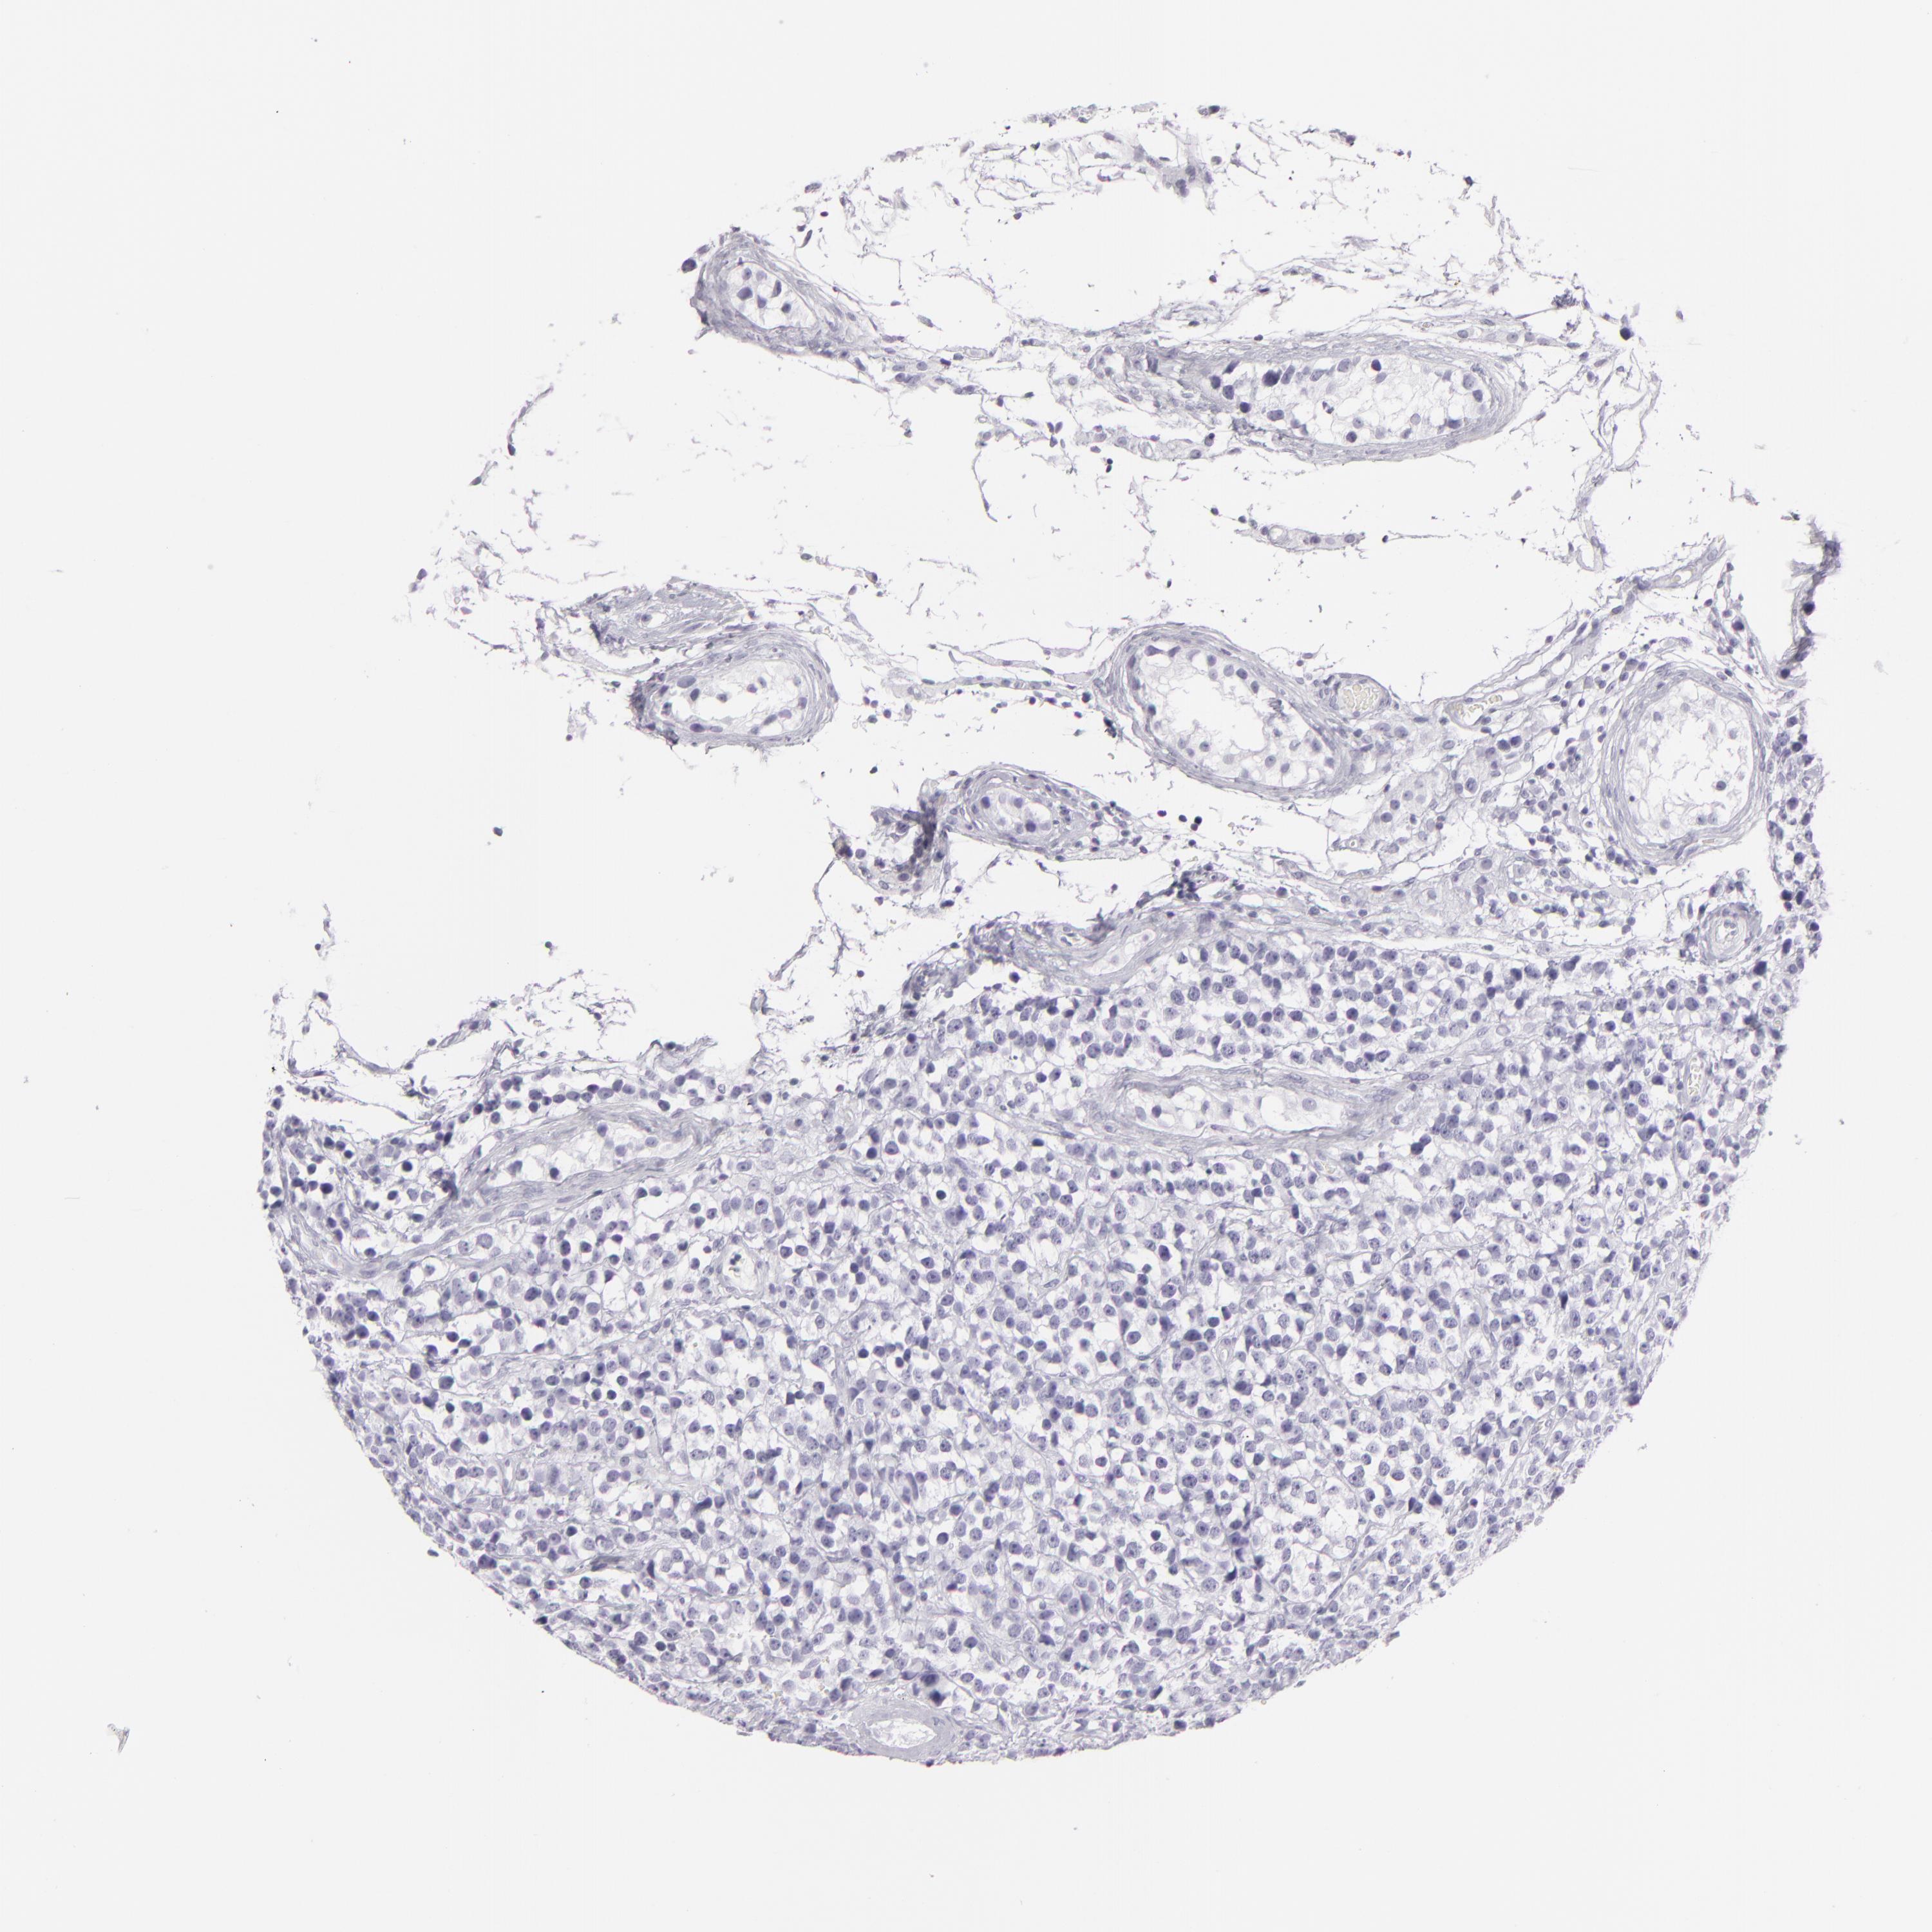

TESTIS CANCER - Protein expressioni

A mouse-over function shows sample information and annotation data. Click on an image to view it in a full screen mode. Samples can be filtered based on level of antibody staining by selecting one or several of the following categories: high, medium, low and not detected. The assay and annotation is described here.

Note that samples used for immunohistochemistry by the Human Protein Atlas do not correspond to samples in the TCGA dataset.

Antibody stainingi

Antibody staining in the annotated cell types in the current human tissue is reported as not detected, low, medium, or high, based on conventional immunohistochemistry profiling in selected tissues. This score is based on the combination of the staining intensity and fraction of stained cells.

Each image is clickable and will lead to virtual microscopy that enables deeper exploration of all samples and also displays staining intensity scores, fraction scores and subcellular localization as well as patient and tissue information for each sample.

Antibody HPA030188

Antibody HPA030189

Antibody CAB002210

Carcinoma, Embryonal, NOS

Seminoma, NOS